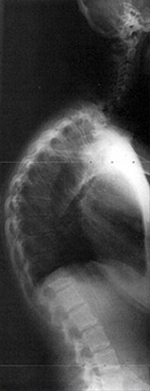

Røntgenbillede af Scheuermanns sygdom

På røntgenbilleder kan man se de typiske kileforandringer af ryghvirvlerne. Baggrunden for at tage et røntgenbillede er typisk en sygehistorie med rygsmerter hos en teenager med forandringer af ryggens krumning.